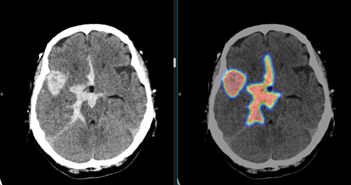

국내의료 인공지능 기업 중 최초로 비급여 보험 수가를 획득한 제이엘케이가 ‘뇌졸중 진단 및 예후 예측 방법 및 시스템’에 대한 유럽 특허 등록에 성공했다고 16일 밝혔다. 이를 통해 세계에서 두 번째로 큰 시장인 유럽 시장을 본격적으로 공략할 수 있게 됐다. 이번 유럽 특허 등록으로 한국은 물론 미국, 일본, 중국에 이어 유럽까지 원천 기술에 대한 특허권을 인정받게 되었으며, 전 세계 시장 진출을 위한 강력한 기술 장벽 기반도 마련되는 쾌거를 거두게 됐다. 이번 유럽 특허 등록이 결정된 기술은 인공지능 알고리즘을 활용하여 뇌졸중 원인과 중증도를 진단하고 예후 예측을 하는 원천 기술들을 포함하고 있다. 특히 이 기술은 현재국내에서는 최초로 비급여처방이 되고 있는 JBS-01K의 기반 기술 특허로 제이엘케이는이 기술을 토대로 매출 성장에 박차를 가하고 있다. 또한, 미국과 일본에서도 이미 특허 등록에 성공하여 이 기술을 활용한 제품들을 통해 현지 시장 진출에 박차를 가하고 있다. 제이엘케이는 지난 9일 ‘2028 JLK AI 비전선포식’에서 뇌졸중의 진단과 치료 전주기에 해당되는 제품군의 고도화된 성능을 소개하고, 국내 병원에서 직접 사용 중인 의료진들이 제이엘케이의 기술이 의료 현장에서 어떻게 사용되고 있는지 실제 증례를 통해 소개하였다. 더욱이 제이엘케이가 제시하는 미래 비전의 가능성과 뇌졸중 패러다임의 전환에 대한 향후 로드맵 및 목표를 발표했다. 국제적으로 우수한 국내 의료환경에서 다양한 영상을 통한 분석 성능 고도화와 각종 의료 정보 시스템과의 자동 연동을 통해 차별화된 사용성을 실현할 수 있었다. 또한 이러한 기술은 뇌졸중 환자의 진단에서 치료까지 전체 프로세스를 대상으로 하는 토탈 솔루션 패키지 제품군으로 미국은 물론이고 일본, 유럽 등 해외 주요 시장을 공략할 예정이다. 제이엘케이 김동민 대표는 “제이엘케이가 뇌졸중 글로벌 No.1 기업이 되기 위해서 지난10년에 걸쳐 뇌졸중 전주기에 대응하기 위한 패키지 제품군을 개발하여 완성 하였다”며 “이러한 전주기 분석이 가능한 제품군을 해외에 납품함으로서 시장 경쟁에서 우위를 지키는 것은 물론, 우리 제품을 써본 의료진은 극대화된 효율성과 치료 효과성을 경험하게되어 충성 고객으로서 시장에 대한 구속력을 높일 수 있는 전략을 구사할 예정이다”고 밝혔다. 뇌졸중 환자를 치료하기 위한 진단 및 치료 과정은 CT, MRI 기반의 다양한 영상과 임상 정보들을 종합하여 판단하기 때문에 고려해야할 범위가 넓고 다양하다. 특히 이러한 다양한 알고리즘을 포함한 원천 기술의 뇌졸중 특허는 타 경쟁사와도 비교될 수 없는 고난도의 기술적 가치로 글로벌 시장 진출의 강력한 기반이 될 것으로 기대되고 있다. 관련 기사 더 보기 https://www.venturesquare.net/906641